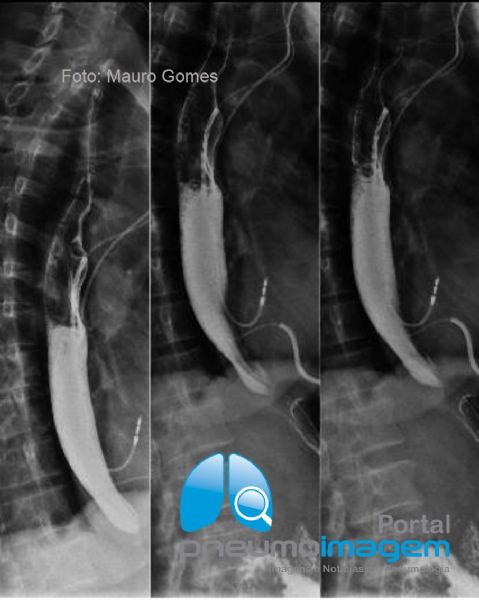

No exame contrastado do esôfago, estômago e duodeno (EED), observa-se o esôfago de calibre moderadamente aumentado e com retardo no esvaziamento. Observe o afilamento do esôfago distal numa extensão aproximada de 1,5 cm e com bordas e relevo mucoso normais, sem sinais de infiltração.

The diagnosis of chagasic megaesophagus was made.Contrasted examination of the esophagus, stomach and duodenum (DSE) shows a moderately enlarged esophagus with delayed emptying. Observe the tapering of the distal esophagus to an extent of approximately 1.5 cm and with normal edges and mucous relief, with no signs of infiltration.

Há peristaltismo aumentado do esôfago distal nos momentos de "espasmo" numa tentativa de esvaziamento, em posição ortostática. Ausência de sinais de hérnia hiatal ou de refluxo gastroesofágico nas diferentes manobras.

There is an increased peristalsis of the distal esophagus in moments of "spasm" in an attempt to empty, in an orthostatic position. Absence of signs of hiatal hernia or gastroesophageal reflux in different maneuvers.